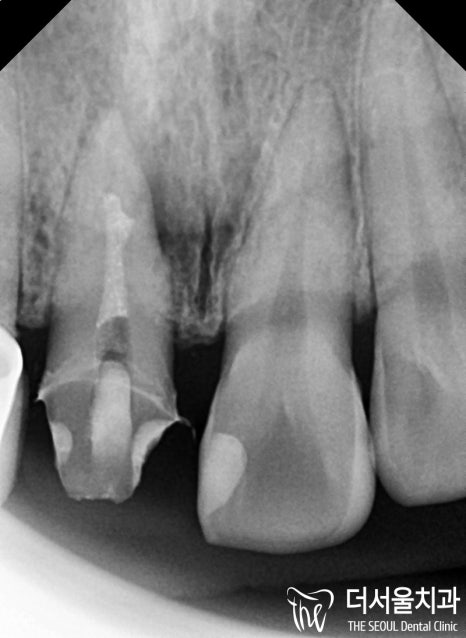

『문제는 부근관』

먼저 치료 결과를 보여드릴게요.

보통 치아의 뿌리의 갯수만큼

또는 형태만큼 신경관이 있는 것이

정상이나 이 분의 경우 기이하게(?)

주 근관에서 따로 나뭇가지처럼

퍼져나가는 부근관이 존재했습니다.

결국, 신경치료를 진행 할 때

이 곳 또한 재료로 꼼꼼히

충전을 시켜야 되는 상황이였죠.

근데 부근관은 실제로 저도

많이 놓치는 치료중에 하나입니다.

신경관의 크기가 0.1mm 가 될 정도로

미세하기 때문에 이런 증세가 있지

않은 이상에는 쉽게 찾아내기가 어렵습니다.